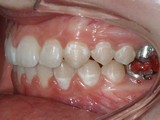

Zkřížený skus, předkus, nedostatek místa pro špičák. Léčba pomocí aparátu Hyrax a dále fixními aparáty v obou čelistech s jumping aparátem. V ústech přítomné MARA-stopy na dočasnou stabilizaci výsledku.

Před léčbou        Po léčbě

pravo pac2       prava pac2